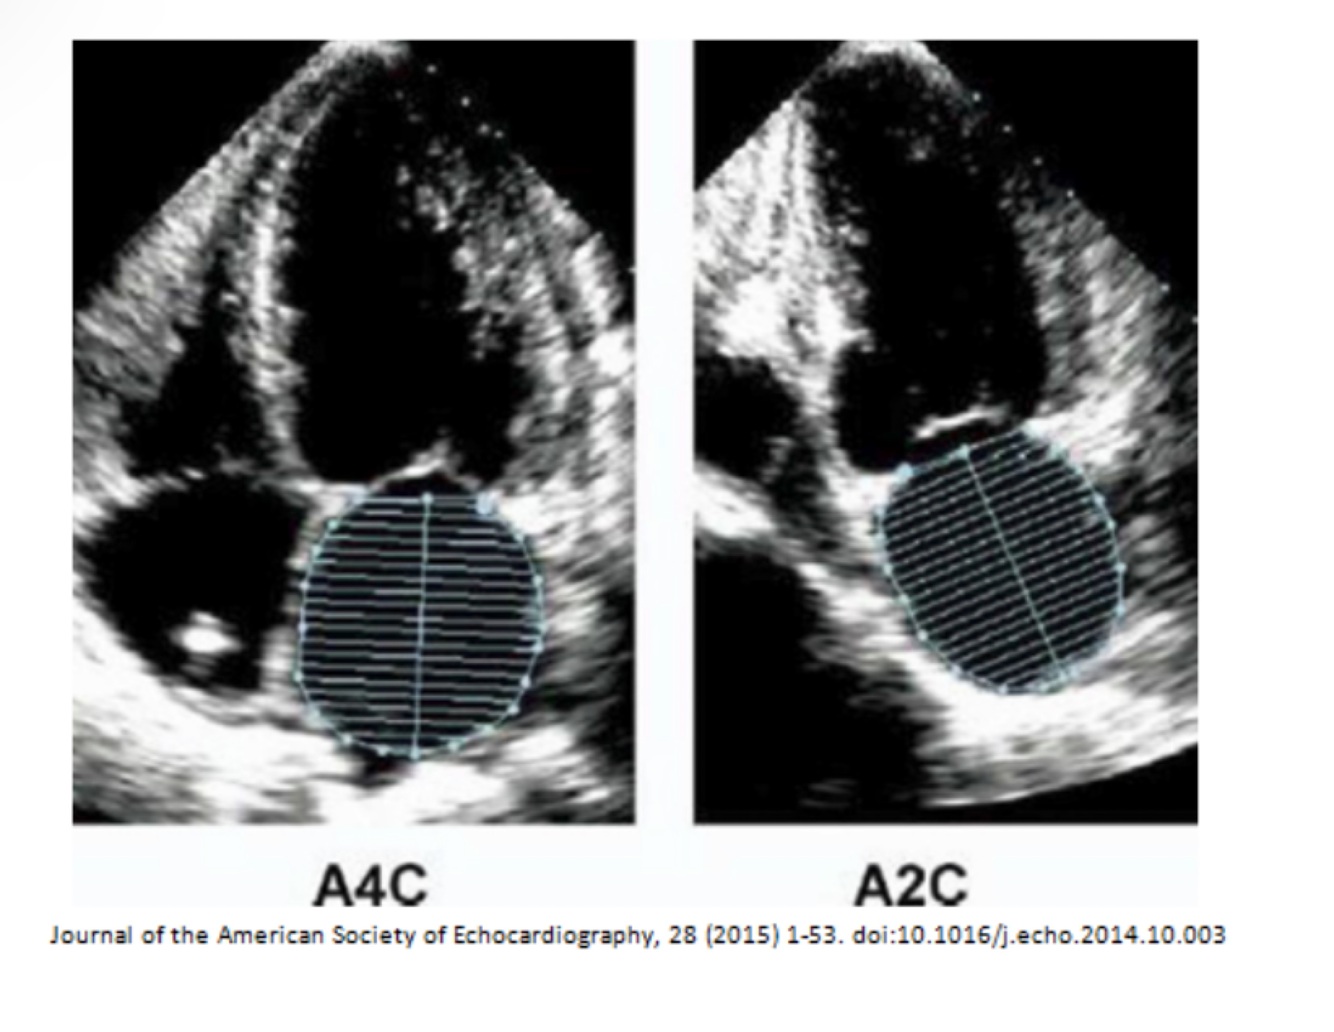

Simpsons BIPLANE method

4 chamber view

-systole and diastole

-do not include papillary or trabeculations

2 chamber view

LVEF = LVEDV – LVESV / LVEDV

LV biplane measurement

Straight line at MV level-height from midpoint Do NOT include papillary muscles or trabelculations No forshortening LV length perpendicular to base